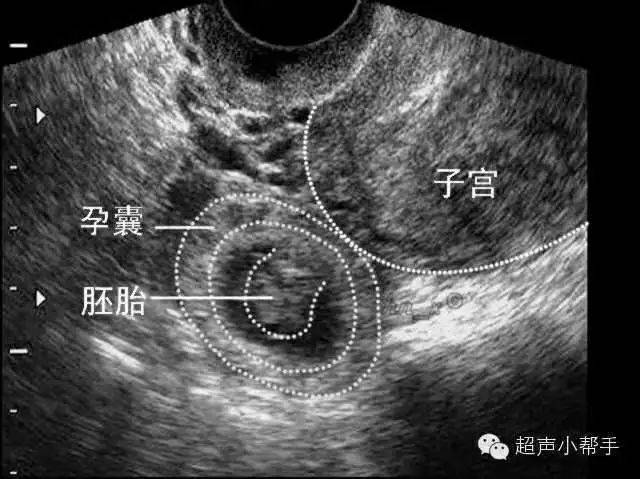

异位妊娠是指孕卵在子宫腔外着床发育的异常妊娠过程,俗称宫外孕,其中以输卵管妊娠最为常见以下是关于异位妊娠的详细解释1 定义与俗称 异位妊娠孕卵在子宫腔以外的部位着床发育,是一种异常妊娠过程 俗称宫外孕2 最常见的类型 输卵管妊娠由于输卵管管腔或周围的炎症,导致管腔通畅不佳。

异位妊娠是指孕卵在子宫腔外着床发育的异常妊娠过程,也称“宫外孕”,以输卵管妊娠最常见以下是关于异位妊娠的详细解释病因常由于输卵管管腔或周围的炎症,引起管腔通畅不佳,阻碍孕卵正常运行,使之在输卵管内停留着床发育,导致输卵管妊娠流产或破裂症状在流产或破裂前往往无明显症状,也可能。